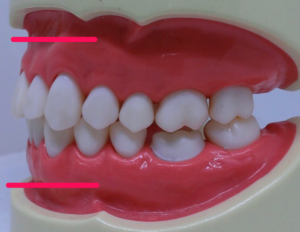

そしてまた、なんでも非抜歯がいいと思っているとこのように、

歯並びは整いますが、噛み合わせも、お顔も、木を見て森を見ず。です。

こうなってからではやり直しは、困難。